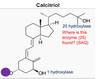

Draw Vit D synthesis

Where does 25-hydroxylation occur?

1-hydroxylation?

Liver

Kidney

What enzyme?

What is the activity of this?

25 hydroxylase

Where is 1 alpha hydroxylase expressed?

Kidney

Rarely in the lung cells of sarcoid tissue

Which is the 1 hydroxlation and 2 hydroxylation?

What is the rate limiting step in Vit D activation?

What controls this?

1 alpha hydroxylation

PTH’s action on the kidneys